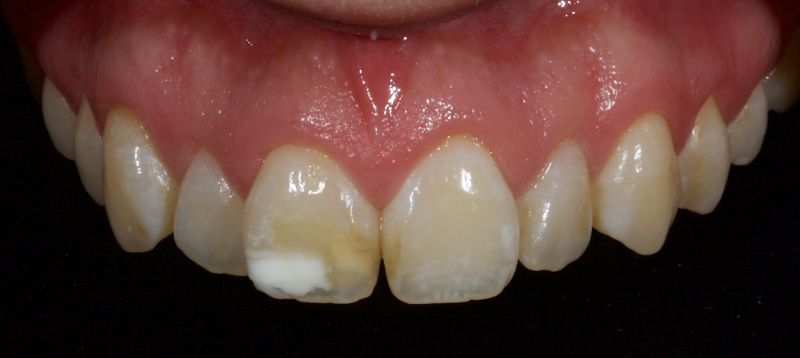

Historically, discolored anterior teeth were treated with indirect ceramic restorations, such as crowns or veneers. This can be illustrated in the case shown in Figure 1, where the discolored left central incisor (2.1), along with two other incisors, was treated with lithium disilicate ceramic veneers (Fig. 2). More recently, direct composite materials that incorporate specialized “opaquers” have also been utilized for treatment.